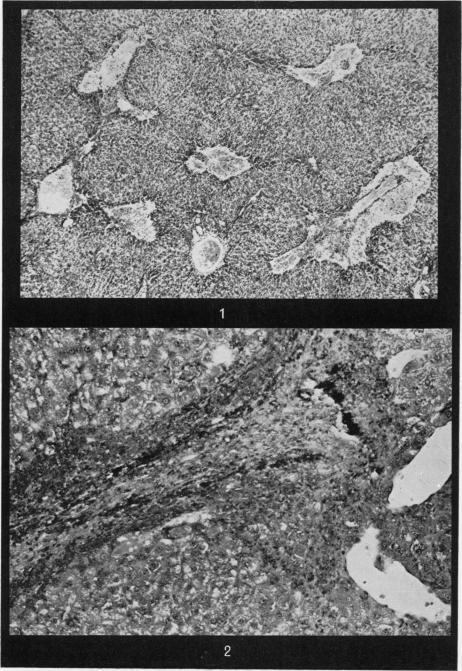

大鼠急性实验性肝静脉闭塞病中的门静脉高压

Portal hypertension in acute experimental veno-occlusive disease of the liver in rats.

Portal pressure was measured in rats 1-14 days after an LD of dimethylnitrosamine (DMN). A significant rise of portal pressure was found at 5 and 7 days after the dose. Veno-occlusive lesions do not occur before 7 days in these animals. Control observations on rats receiving CCl showed no change in portal pressure attributable to centrilobular necrosis. Possible mechanisms for this rise of pressure are discussed.

摘要

在给予大鼠二甲基亚硝胺(DMN)致死剂量后1至14天测量门静脉压力。给药后第5天和第7天发现门静脉压力显著升高。在这些动物中,静脉闭塞性病变在7天前不会出现。对接受四氯化碳(CCl)的大鼠进行的对照观察显示,由于小叶中心坏死,门静脉压力没有变化。文中讨论了这种压力升高的可能机制。